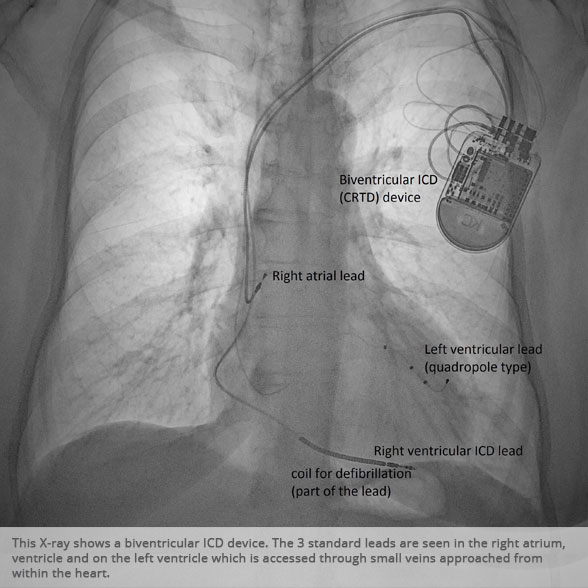

Biventricular ICD (CRTD) Biventricular ICD (CRTD)

Biventricular ICD (CRTD) device Biventricular ICD (CRTD) device

Above: Slideshow containing X-rays of common medical procedures.

BI-VENTRICULAR PACEMAKERS

Bi-ventricular pacemakers are used for the treatment of suitable patients with heart failure who are already on medication but who suffer from a lack of synchrony between the right and left ventricular contraction. This is most commonly caused by an electrical delay (left bundle branch block LBBB) in transmission of signals to the main pumping chamber (called the left ventricle) and is relatively common in patients with advanced heart failure. This delay process commonly worsens the symptoms of heart failure and it is not generally influenced by medication alone.

Although not all patients universally respond to bi-ventricular pacing (or cardiac resynchronisation therapy/CRT), patients with more advanced dys-synchrony tend to experience remarkable improvement. Bi-ventricular ICDs have the additional benefit of recognising life threatening arrhythmia and deliver both fast pacing bursts or shocks to restore normal heart rhythm.